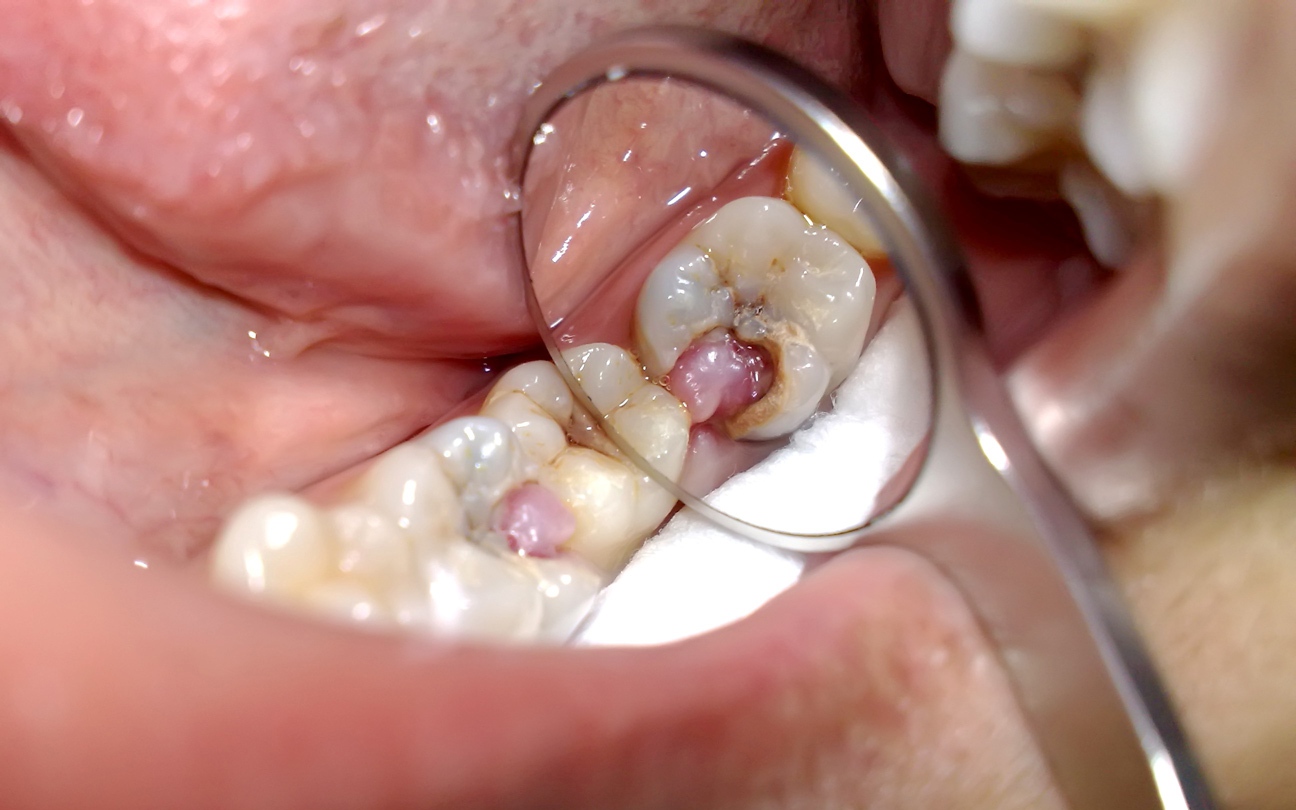

1. Sâu răng

Sâu răng là bệnh lý phổ biến trong cộng đồng, do vi khuẩn trong mảng bám gây ra. Sau mỗi bữa ăn, nếu vệ sinh răng miệng không kỹ, vi khuẩn sẽ phân hủy đường và tinh bột còn sót lại, sản sinh acid ăn mòn men răng.

Giai đoạn đầu, sâu răng chỉ gây ê buốt nhẹ khi ăn đồ ngọt hoặc uống nước lạnh. Tuy nhiên, khi tổn thương lan qua lớp men và ngà răng, tiến sát buồng tủy, dây thần kinh bị kích thích, người bệnh có thể xuất hiện:

Khi sâu răng đã chạm đến tủy, cơn đau thường dữ dội hơn vào ban đêm, khiến người bệnh khó ngủ hoặc thức giấc giữa chừng.